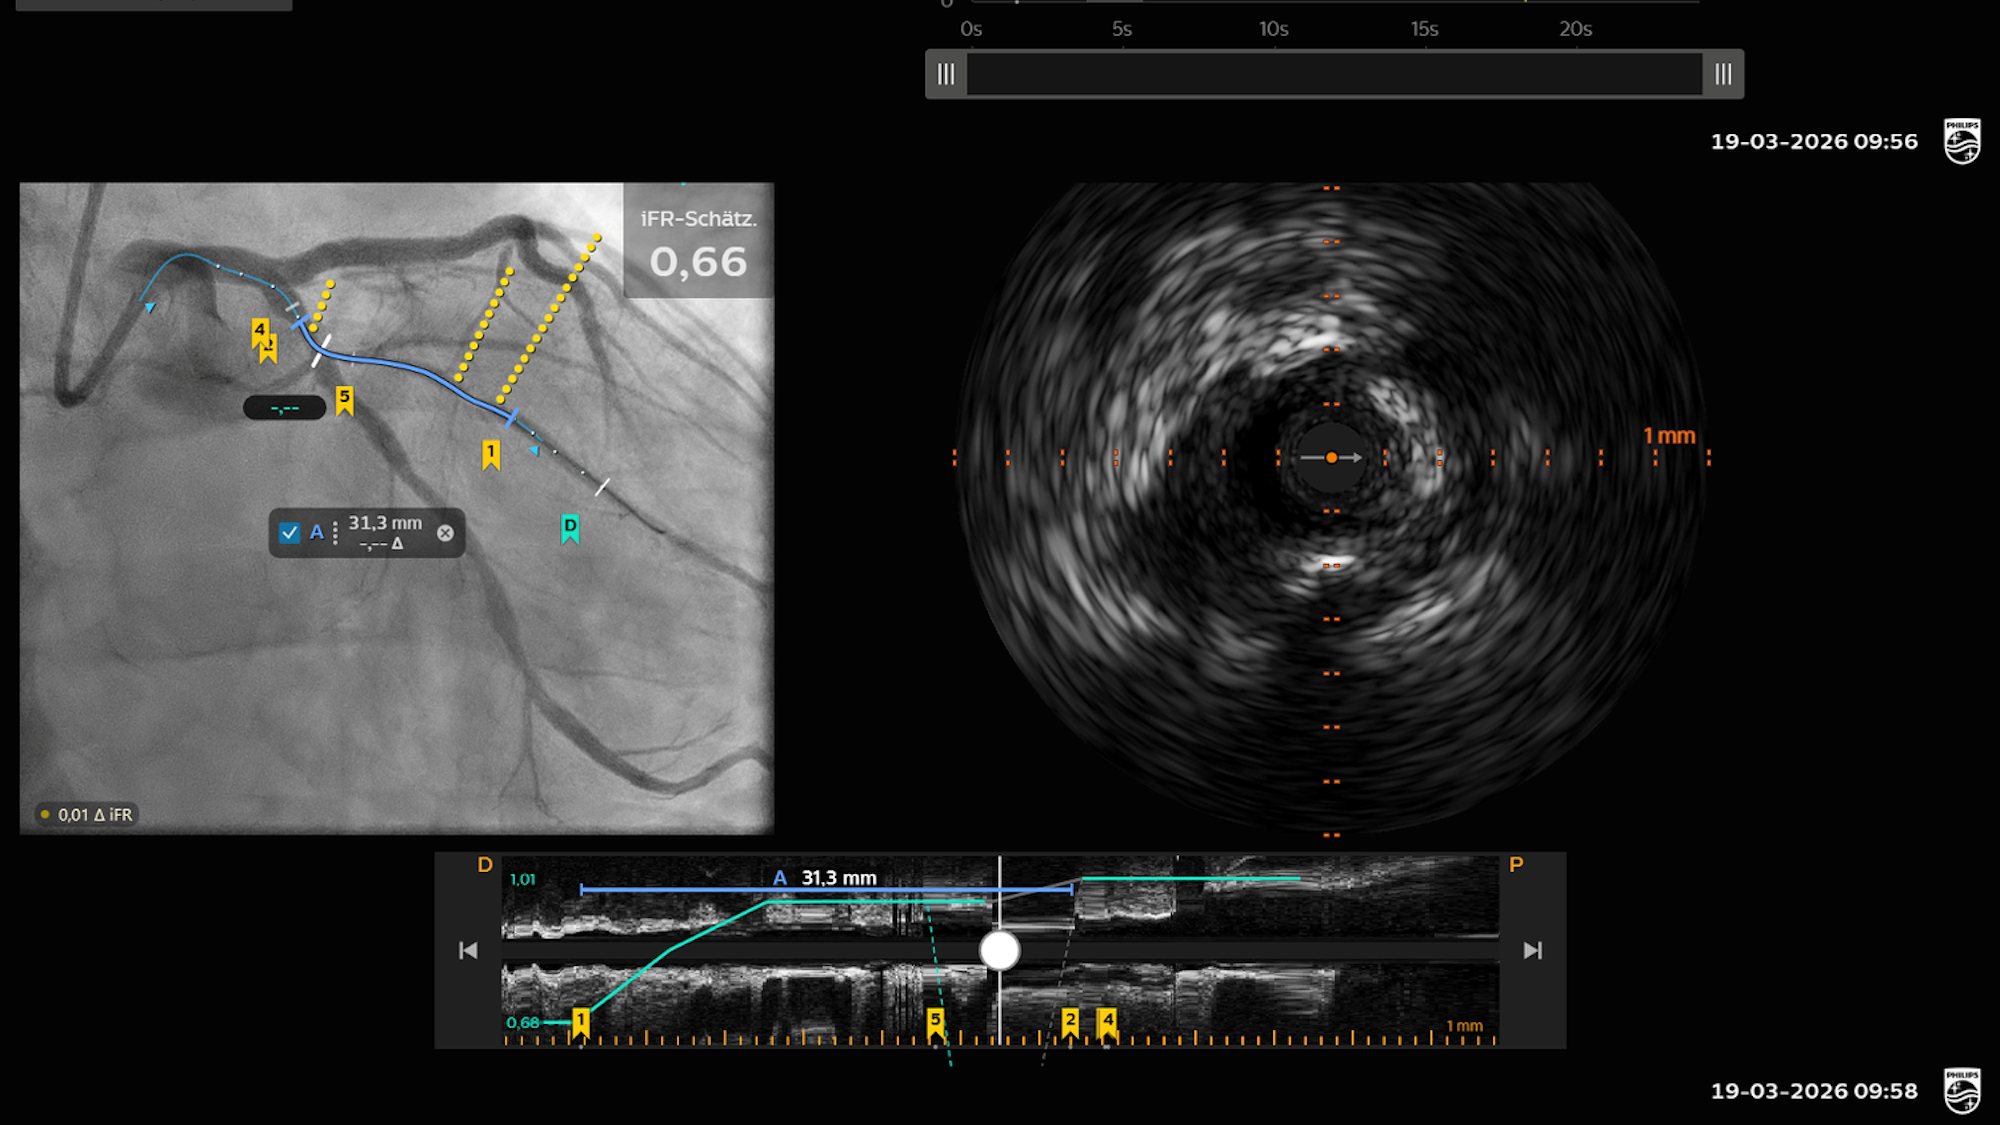

Herzkatheteruntersuchung mit der neuen Diagnose-Plattform „IntraSight Plus“ von Philips im Kölner St.-Vinzenz-Krankenhaus.

Der Mann war erfolgreich reanimiert und mit einer ersten Herzkatheter-Behandlung, bei der drei Stents eingesetzt wurden, stabilisiert worden. Dabei habe man jedoch zwei weitere höhergradige Engstellen gefunden. Diese wurden dann am Donnerstag beim ersten Einsatz der „IntraSight Plus“ von Philips behoben. Das neue System habe sich hierfür besonders angeboten, „weil man ganz besonders gut drei Modalitäten für die optimale Behandlung miteinander kombinieren kann“, sagte Sinning. „Die Gefäßdarstellung, also die Angiographie, die Messung des Blutflusses vor und hinter der Engstelle, genannt Hämodynamik, und die Ultraschalluntersuchung im Gefäß.“

Mit diesen drei in einer Darstellung vereinten Parametern lasse sich sehr genau bestimmen, wie groß und wie lang eine Engstelle ist. „Wir konnten perfekt sehen, wie die Engstelle aussieht und danach bestimmen, wie der Stent beschaffen sein muss“, erklärte Sinning: „Kurz bedeutet das: weniger Stents, optimale Platzierung, länger infarktfrei.“ Auf die Erstinstallation in Köln sei man sehr stolz, hieß es in einer Mitteilung des St. Vinzenz: „Das zeigt das besondere Vertrauen in unsere kardiologische Expertise und den Standort Deutschland.“